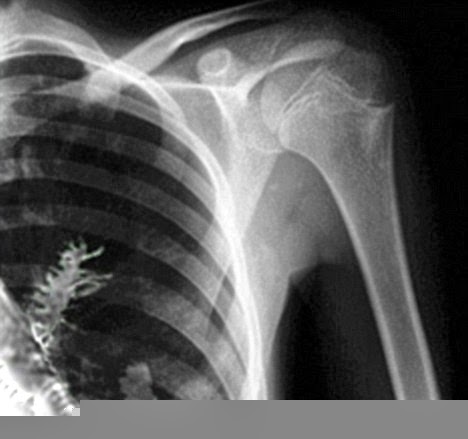

pois tossia sangue e tinha dores no pulmão, o primeiro diagnostico do raio-X

indicava o que parecia ser um tumor, então o médio decidiu opera-lo

| Os primeiros exames apontavam um tumor |